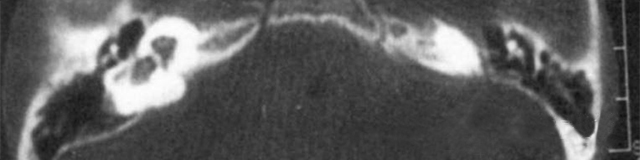

1、診斷

主要依靠顳骨高分辨CT和內耳MRI。

雙側內耳畸形:左側無內耳迷路及內耳道機構,為米歇爾畸形;右側空耳蝸及前庭擴大,為先天性耳蝸畸形